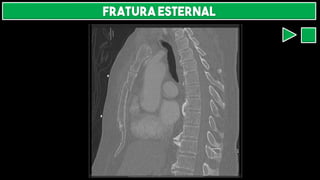

FRATURA ESTERNAL